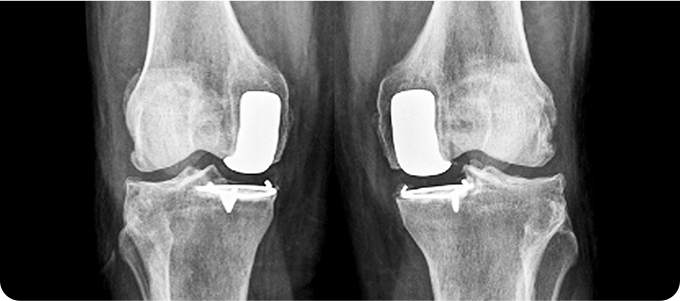

무릎 관절염

인공관절치환술

퇴행성 관절염으로 닳아버린 연골과 변형된

뼈 표면만을 정밀하게 절제합니다.

무릎의 굽힘·펴짐과 안정성을 고려해

인공관절을 삽입, 무릎 중심축을 바로 잡아줍니다.